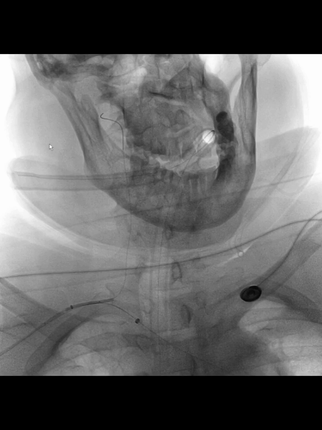

右股动脉穿刺置8F短鞘,5F长多功能管(125cm)和6F长鞘(90cm,Cook)组成同轴,导丝导引下5F管头端进入右锁骨下动脉。

长鞘跟进到右锁骨下动脉近端。

5F管沿导丝送至右腋动脉,经此管送入一.018"导丝(Command 18),其头端置于右肱动脉远端,保留导丝,交换出5F管,.018"导丝作悬吊支撑用。

微导管(Rebar 18)配合微导丝(Command 14)尝试超选右椎动脉,但微导丝头端难以通过V1的曲折管腔;后长鞘内衬一4F长多功能管增强支撑和指向性,但微导丝仍然难以克服右V1的曲折。

微导丝头端改塑形状后,还是克服不了右V1曲折。